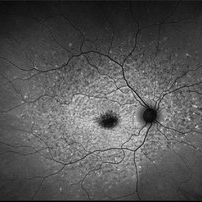

Late Stage Stargardt's Disease

Late Stage Stargardt's Disease

Mar 13 2013 by Hamid Ahmadieh, MD

Autofluorescence imaging of the right eye of a 46-year-old man with decreased VA due to advanced Stargardt's disease.

Photographer: Nayereh Hadipoor, Negah Eye Center, Tehran

Imaging device: Heidelberg Spectralis

Condition/keywords: autofluorescence imaging, Stargardt disease